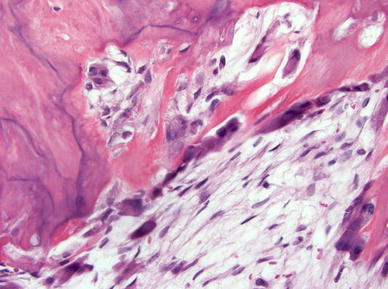

A panoramic radiograph revealed a well-defined, radiopacity with a surrounding peripheral radiolucent zone partially obscuring and resorbing the roots of the left mandibular first molar (Fig. 1).

Fig. 1

Round radiopacity with radiolucent rim at the apical region of left mandibular first molar tooth